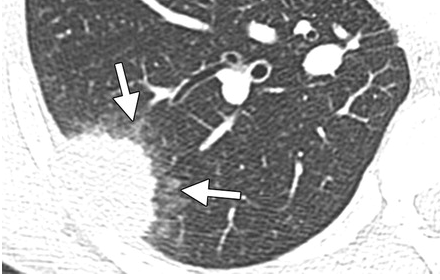

- Multiples nodules aléatoires de taille variable (2 - 10 cm), à bords irréguliers

- Cavitation dans les nodules de grande taille (contrairement au DD: Nodules cavitaires de PR)

Avec petites plages de VD hemorragique